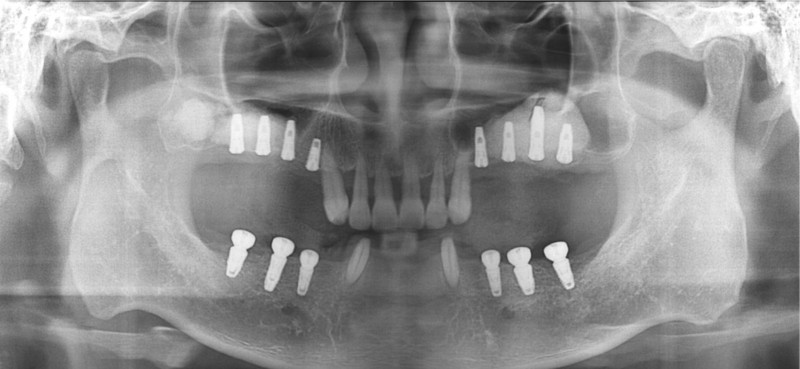

중간과정 ▼